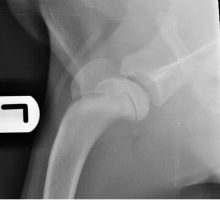

Gus is doing well following bilateral hip replacements

It was great to see Gus back in the clinical last week for his x-rays 6 weeks after the ...